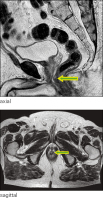

Abbildung 4: MRT axial und sagittal 11/2012 (T2-Gewichtung)

MRT

Onkologie

Rektum

SMT

submukosaler Tumor